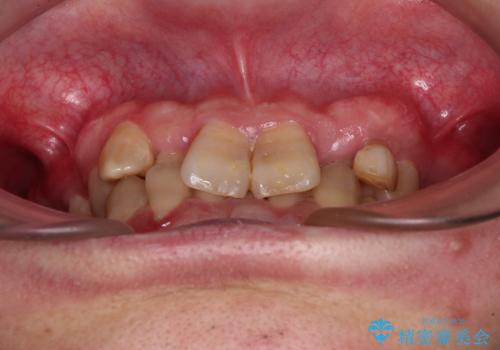

- 上下の前歯のデコボコを改善したいと来院された患者様です。

上顎の歯列幅が狭く、それによって歯が並ぶスペースが不足しています。

また下顎の歯列幅も制限され、内側に歯が倒れています。

左上の乳犬歯は当初保存する計画でしたが、虫歯が大きいため抜歯になり、患者様の希望によりブリッジにしました。